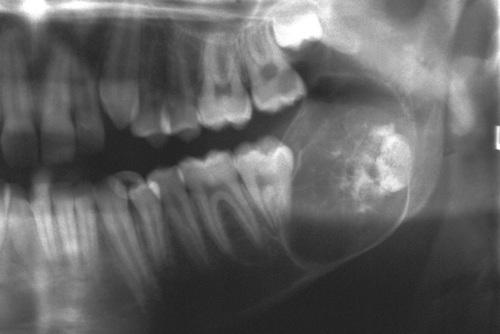

Radiographic Features

- well-defined radiolucent area

- large lesions may appear multilocular

- smooth and often corticated margins

- growth in an anteroposterior direction

- may involve an unerupted tooth (25% to 40%)

This large, multilocular cyst involves most of the ascending ramus and is growing in an anteroposterior direction.

odontogenic keratocyst (OKC)